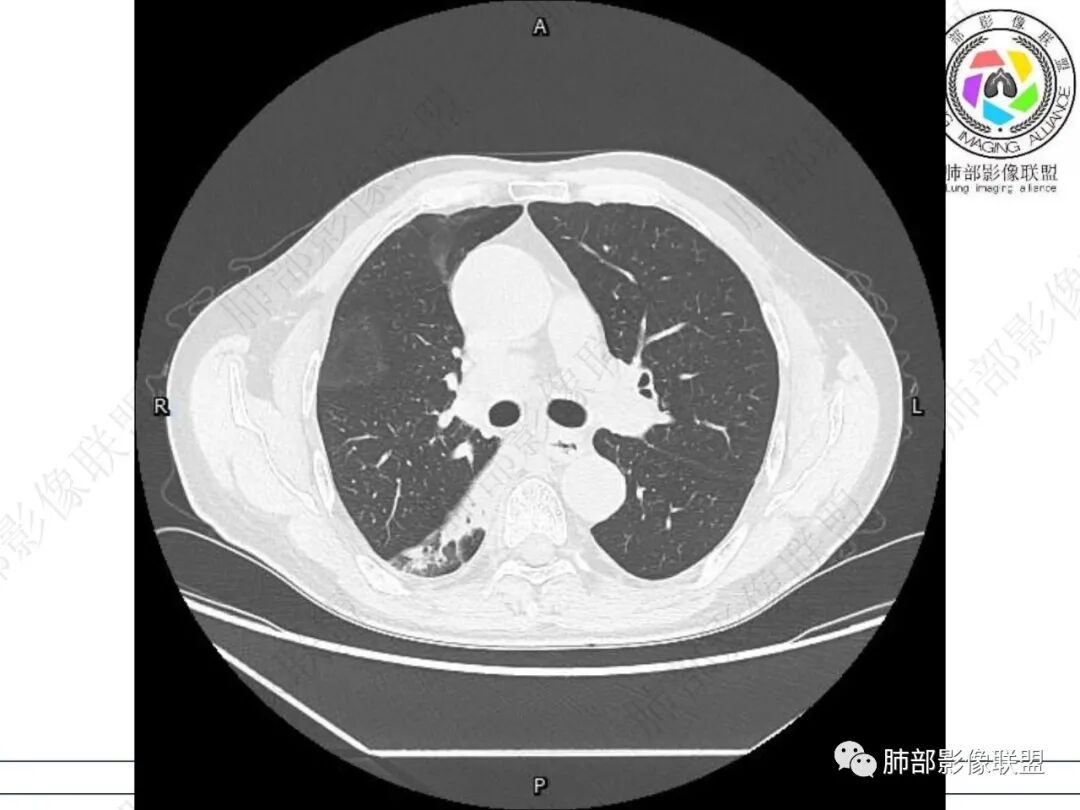

右肺下叶背段可见斑片状、条片状高密度影,支气管扩张,周围伴有磨玻璃影,边界欠清,纵隔窗:可见脊柱偏右侧可见斑片状影,与食管交界面欠清,食管形态不规则,考虑食管支气管瘘?食管异物穿孔?支气管异物?建议食管镜及支气管镜检查。

右肺下叶背段条片状实变影,内可见支气管走行,支气管有狭窄有扩张,周围可见磨玻璃影,隆突下团片影,内密度不均可见气体影,与周围结构界限不清。食管下段壁增厚,管腔狭窄,右肺下叶慢性炎、肺不张,考虑食道肿瘤所致气管食管瘘。

右肺下叶沿肺叶肺段分布斑片、条片状影,以下叶背段为显,边缘模糊,内可见支气管走行,局部支气管管壁增厚,右侧胸腔少量积液。纵隔隆突下可见不均匀软组织密度影,与周围结构分界不清,内见气体密度影,与食管及相邻右肺支气管之间未显示通道。邻近食管下段壁明显不规则增厚,增强后食管管壁明显不均匀强化,可见线样强化的连续完整粘膜影。